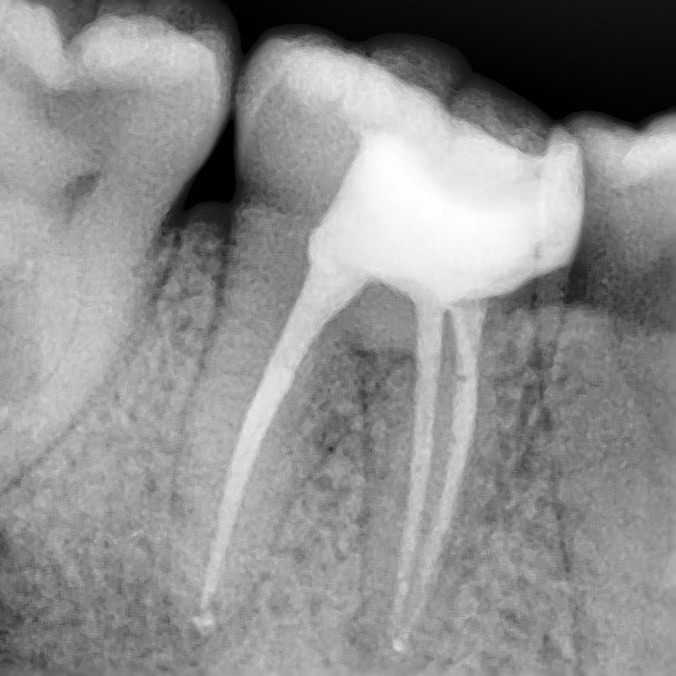

precise determination of the shape of the channels

High-precision X-ray shows the shape of the canals and the area of inflammation

We pay great attention to the procedure of root canal treatment, so we have established the detailed protocol of root canal treatment which provides thorough removal of all the organic elements which may cause inflammation and in six months after completion of treatment we also provide repeated X-rays examination to control hermicity of canal filling and absence of reinfection.

control x-ray